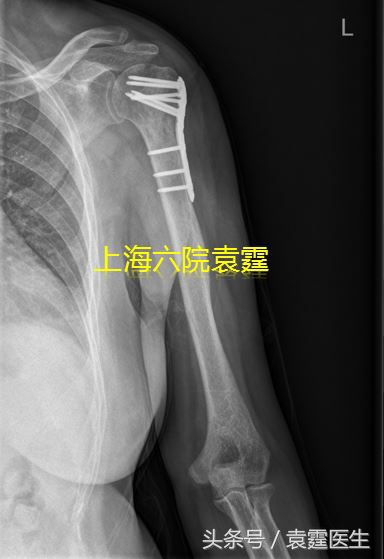

良性的或低度恶性的肿瘤,一般只要把肿瘤刮除,然后在肿瘤刮除后残留的空腔里植骨,钢板螺钉固定就可以了,复发率比较低,而且病人能完全恢复。

良性骨肿瘤刮除植骨骨固定术后